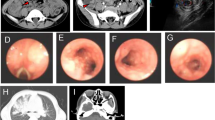

The patient is a 13-year-old boy, presenting with intermittent fever for 5 months, who also experienced diffuse lymphadenopathy, arthritis, and recurrent multiple gastrointestinal ulcers. EBV DNA was detected in the serum and peripheral blood mononuclear cells of the patient. The immunological phenotype showed increased proportion of double-negative T cells (CD3+CD4−CD8−). A novel missense mutation (c.1428G > A) locating at the zinc fingers 2 (ZF2) domain of TNFAIP3 inherited from his mother was confirmed. Compared with age-matched healthy controls, decrease expression of A20 was observed in the patient. The NF-κB pathway was found to be overactivated, and the synthesis of TNF-α was upregulated in the patient-derived cells. However, cells from the mother showed a milder response to LPS than cells from the patient.